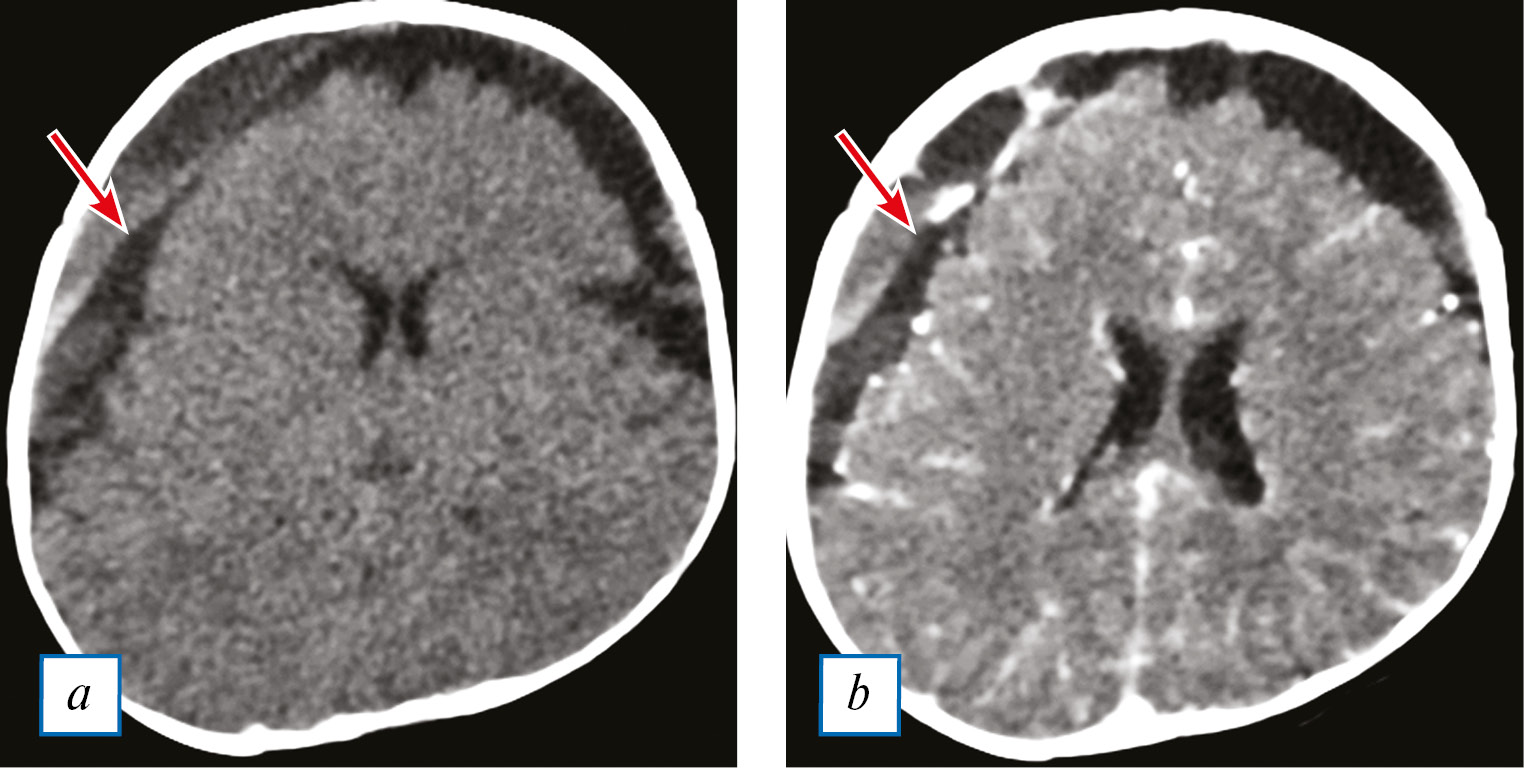

Приблизительно у 55–70% пациентов с клинически доказанным менингитом при внутривенном контрастировании возможно обнаружение тонкого линейного накопления контрастного вещества в бороздах коры головного мозга [5].На сегодняшний день показано, что чувствительность импульсных последовательностей FLAIR и DIR (double inversion recovery — восстановление двойной инверсии) в выявлении патологических изменений в оболочках головного мозга превосходит чувствительность T1-взвешенных изображений (Т1-ВИ) вследствие подавления МР-сигнала от нежелательных тканей и меньшей зависимости от неоднородности магнитных полей [14] (рис. 1).

Рис. 1. МРТ головного мозга пациента в возрасте 3 лет с бактериальным менингитом. Диффузное усиление МР-сигнала в FLAIR-режиме в области борозд мозга (a), изоинтенсивное — в режиме DWI (100 с/мм2) (b), без МР-признаков накопления контрастного вещества (c). Фокальные субкортикальные изменения без признаков повреждения гематоэнцефалического барьера (собственные данные).

Fig. 1. Brain MRI of a 3 year-old patient with bacterial meningitis. Diffuse increase in the MR signal in the FLAIR mode in the furrows of the brain, isointense in the DWI mode (1000 s/mm2), no signs of the contrast accumulation. Focal changes in the subcortical parts of the brain without signs of blood-brain barrier disturbance.